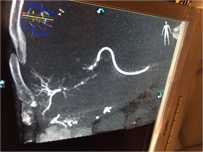

XperGuide Ablation enables real-time needle guidance in the angio suite. Virtual needle paths are created by overlaying previously acquired MR or CT datasets with XperCT data to enable optimal planning of one or multiple needles for full tumor coverage. XperGuide Ablation supports all ablation techniques (such as RF, microwave and cryo-ablation) by displaying the isotherm of the ablation needles.